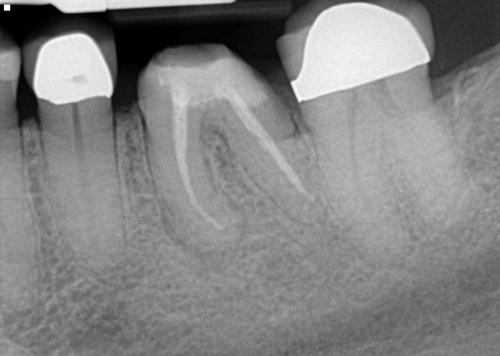

The idea that a dentist may be incorrect in his or her diagnosis is distasteful, but a reality that this profession wrestles with on a daily basis. An image comparison can help to clarify this thought. The first image is a 2D radiograph of tooth No. 19 that includes the buccal cortical plate the lingual cortical plate and approximately 10 mm of trabecular bone compressed into a single image (Figure 1). Because the full width and volume of the tooth is included in the image, any existing pathoses could be masked or hidden in a fog of digital information. A CBCT scan of the same tooth provides more detail because it can present a slice (0.1 mm) of information from the center of the area in question (Figure 2). All of the extraneous information is eliminated, and the clinician and the patient have a more precise picture to evaluate. Furthermore, a periapical radiograph can be distorted by the angle of the cone to the sensor, whereas a CBCT scan has no distortion and is accurate in all views. With a CBCT scan, the clinician is able to state with certainty that a condition exists, and the patient is able to more clearly understand what his or her condition is when considering the available choices for treatment.

(1. ) Two-dimensional periapical radiograph of tooth No. 19 compared with a CBCT scan slice (0.1 mm) of the same tooth, which reveals a well-defined lesion that a patient can more easily understand.

Figure 1

(2.) Two-dimensional periapical radiograph of tooth No. 19 compared with a CBCT scan slice (0.1 mm) of the same tooth, which reveals a well-defined lesion that a patient can more easily understand.

Figure 2